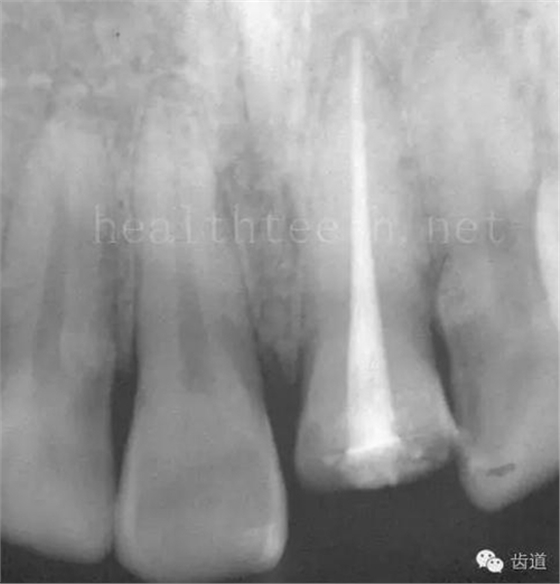

因?yàn)楸旧聿桓阏衬げ。占降牟±邢?,大多是同事收?/span> 頰粘膜扁平苔蘚 舌粘膜扁平苔蘚 舌緣創(chuàng)傷性潰瘍 長期戴活動義齒不當(dāng)或是戴不良修復(fù)義齒造成的口腔粘膜潰瘍,應(yīng)該引起高度警惕,因?yàn)檫@種潰瘍?nèi)菀装┳?/span> 黑毛舌 舌息肉,該患者同時伴有胃、食管息肉,后來看內(nèi)科了,具體情況不詳 四、孩子的牙齒問題 乳牙未退,牙根穿出牙齦對上唇粘膜造成刺激 乳牙滯留,也是孩子在退牙過程中最容易遇到的問題 五、牙齒發(fā)育上的問題 變色牙 氟斑牙 釉質(zhì)發(fā)育不全 四環(huán)素牙 牙神經(jīng)治療后的牙齒變色 10歲孩子剛剛萌出的牙齒變色 2、埋伏牙 左上乳3滯留,恒3未見萌出,曲面斷層片顯示牙齒埋伏 通過CT片確定埋伏牙齒具體的位置,顯示距離左側(cè)上頜竇很近,偏唇側(cè),這為手術(shù)定位提供了方便 手術(shù)中切斷、完整拔出,未損傷上頜竇 其他埋伏牙 3、多生牙 病例1 病例2 病例3,同時多生兩顆牙齒 4、各種畸形牙 畸形過小牙 融合牙:恒牙和乳牙都可以發(fā)生融合的情況(兩顆牙齒長在了一起) 畸形中央尖:在牙齒的中央,兩個牙尖之間又多長出一個牙尖,由于進(jìn)食的磨耗很容易造成磨穿,神經(jīng)就會與外界相通,出現(xiàn)牙髓炎的癥狀 六、牙齒的外傷 牙冠折斷 牙根折斷 烤瓷牙打樁修復(fù)后牙根折斷 外傷后牙齒的全脫位,應(yīng)該保留牙齒盡早做再植手術(shù) 七、牙齒的慢性損傷 牙頸部楔狀缺損 牙冠劈裂及完整拔除后的情況 牙根縱裂及拔除后的情況 牙隱裂,牙齒表面有肉眼看不到的裂紋,細(xì)菌通過其進(jìn)入牙髓,容易出現(xiàn)牙髓炎癥狀,嚴(yán)重可以造成牙齒的劈裂 這是一位來中國學(xué)習(xí)的俄羅斯大學(xué)生的牙齒,已經(jīng)做過了根管治療,牙齒咬合面有隱裂,通過鋼絲結(jié)扎固定,做鑄造金屬冠修復(fù)。 八、牙髓炎、根尖周炎 下面圖片都是慢性根尖周炎的病例,有了齲齒,進(jìn)一步發(fā)展就是牙髓炎,如果此時沒有得到及時的治療,疾病會逐漸發(fā)展破壞到根尖的骨質(zhì),將骨質(zhì)破壞后就在牙齦上出現(xiàn)一個膿瘺,此時患者不再感覺到牙齒的疼痛了,往往忽視了治療,但是這種不痛并不是疾病好轉(zhuǎn)了,而是因?yàn)榧膊〉难仔詽B出得到了引流,這個膿瘺會出現(xiàn)有時候變大了,有時候又變小了,但是如果不治療是不會自己愈合的,只有經(jīng)過完善的根管治療后才有好轉(zhuǎn)的可能,但是在疾病的治療中時間是起決定作用的,時間拖得越晚,好轉(zhuǎn)的可能性越小,經(jīng)過根管治療后如果膿瘺還是沒有消失,就需要做根尖刮治術(shù),如果仍然沒有好轉(zhuǎn),就只能做根尖切除術(shù)了,這對牙齒的穩(wěn)固是不利的。下面圖片中在膿瘺中插入了一個牙膠尖,是我們做根管充填用的材料,是非常軟的,就是在口腔牙齦瘺管的地方插進(jìn)去,通過拍牙片可以清晰地看到它到達(dá)的位置,從而確定發(fā)病的牙齒,此處是為了讓大家看得更清楚。 門牙兩個膿瘺 烤瓷牙修復(fù)后牙齦出現(xiàn)兩個膿瘺,插入牙膠尖,牙片顯示牙膠尖到達(dá)的位置就是根尖炎癥的位置,根尖骨質(zhì)密度降低(發(fā)黑的地方) 牙齒根尖膿瘺,治療前、中、后的圖片對照,完善根管治療后膿瘺明顯消失了 牙髓炎和根尖炎治療的關(guān)鍵就是根管治療 合格的根管充填治療 不良的根管充填治療 九、關(guān)于智齒(第八顆牙) 四顆長不出來的智齒 智齒反復(fù)發(fā)炎造成的頰瘺,膿腫切開引流后面部會留疤 智齒造成的頜骨囊腫,手術(shù)切除后需要植骨 十、各種錯合畸形 開合 深覆合 深覆蓋,上頜前突 反合(地包天) 牙齒排列擁擠 來源:牙醫(yī)愛看的 KQ88口腔醫(yī)學(xué)網(wǎng)